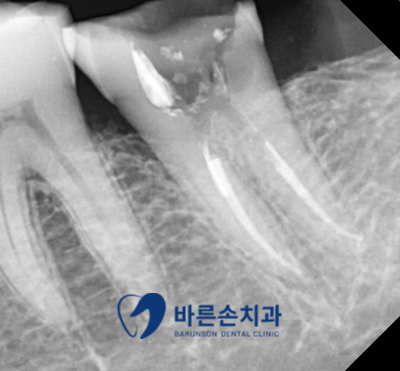

환자분의 구강 내 사진입니다

사진에서 보시다시피 치아에 구멍이 크게 있고

그로 인해 음식물도 많이 끼고 불편감이 있다고 하십니다

충치도 많이 진행이 된 상태입니다.

정확한 손상 범위를 알기 위해 엑스레이 촬영을 진행하였습니다

엑스레이 촬영을 해본 결과

치아의 신경관 가까이까지 충치가 진행되어 있는 것을 알 수 있습니다

신경 치료를 진행하기로 하였습니다ㅜㅜ